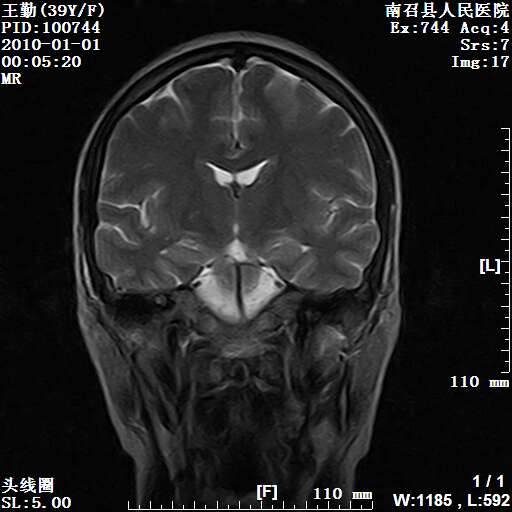

以下是引用随光逐影在2010-1-22 9:03:00的发言:[br]考虑左侧中颅窝(蝶骨翼区)脑膜瘤侵犯蝶骨翼并突入左侧眼眶。

以下是引用水过无痕在2010-1-22 14:55:00的发言:[br]一、定位:颅外占位;二、定性:恶性可能性大;三、组织来源:来源于左侧眼外直肌或其他部位;考虑为:横纹肌肉瘤>转移瘤>脑膜瘤.